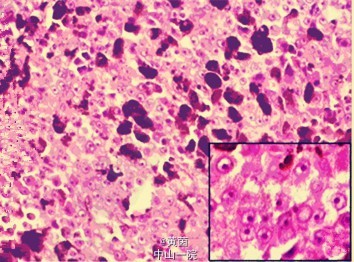

全身查体: 全身皮肤黏膜未发现黑痣溃烂,全身浅表淋巴结未触及明显肿大。 妇科查体: 右侧外阴发育正常,左侧外阴小阴唇缺如,大阴唇内侧可见一约4cm竖形疤痕,愈合良好,无溃烂,无红肿发炎,阴道通畅,宫颈光滑,正常大小,子宫前位,正常大小,无压痛,双侧附件区无压痛,未触及包块。 辅助检查: 外院病理:交界痣恶变-恶性黑色素瘤,切缘阳性。 CEA:5.1ng/ml(正常值0-5ng/ml),CA-199、CA-125、HE4、AFP、HCG 均在正常范围内。血常规、肝肾功能指标未见明显异常。 免疫细胞化学结果显示 HMB45、S-100、CD56、CD99、EMA 阳性,PAS 阴性。胸片、妇科B超未见明显异常,头颅CT及骨扫描检查未发现病灶

患者目前诊断为:外阴恶性黑色素瘤II期 入院后完善相关检查,因患者术后病理提示:交界痣恶变-恶性黑色素瘤,切缘阳性。于2014-7-25在全麻下行双侧腹股沟淋巴结清扫术加外阴局部广泛切除术,术前考虑患者年纪较轻,对于术后外阴外观要求较高,已请整形外科术中予以会阴部皮瓣设计,协助术后切口的缝合。术中行冰冻病理检查,结果显示:交界痣恶变-恶性黑色素瘤,左侧切缘阴性,右侧切缘阴性。术后留置尿管,为预防外阴血肿,先予以加压包扎。出院时患者切口愈合良好,对手术效果满意,回当地医院辅以化疗。 术后诊断为:外阴恶性黑色素瘤II期 术后石蜡病理:交界痣恶变-恶性黑色素瘤,切缘阴性。